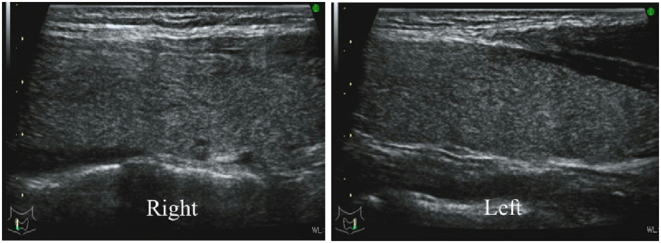

Methods and results: Seven patients diagnosed with SAT during pregnancy at our institution from January 2004 to December 2021 were identified, and their clinical findings were retrospectively examined. At SAT diagnosis, the median age was 34 (range: 31-42) years, the median duration of pregnancy was 5 (4-24) weeks, and all patients had neck pain but no fever. On laboratory examination, median (range) free thyroxine, free triiodothyronine, and C-reactive protein levels were 2.66 (1.14-7.77) ng/dL, 7.1 (3.3-16.1) pg/mL, and 2.22 (0.42-5.79) mg/dL, respectively, and all patients had a hypoechoic lesion of the thyroid gland. Three patients (43%) were treated with steroids, and three patients (43%) received replacement therapy with levothyroxine for hypothyroidism following destructive thyroiditis. There were no pregnancy complications in any of the cases. These seven patients (pregnancy group) were compared with 217 non-pregnant female patients (non-pregnancy group) aged 31 to 42 years who were diagnosed with SAT at our institution from 2016 to 2019. The frequency of body temperatures above 37°C was lower in the pregnancy group than in the non-pregnancy group (0% vs 65%).

目的:关于妊娠期亚急性甲状腺炎(SAT)的报道很少。本研究旨在阐明妊娠期亚急性甲状腺炎的临床特征:方法:研究人员对我院 2004 年 1 月至 2021 年 12 月期间确诊的 7 例妊娠期亚急性甲状腺炎患者的临床表现进行了回顾性研究。确诊 SAT 时,中位年龄为 34 [31-42]岁,中位孕期为 5 [4-24] 周,所有患者均有颈部疼痛,但无发热。实验室检查结果显示,游离甲状腺素、游离三碘甲状腺原氨酸和C反应蛋白水平的中位数(范围)分别为2.66(1.14-7.77)纳克/分升、7.1(3.3-16.1)皮克/毫升和2.22(0.42-5.79)毫克/分升,所有患者均有甲状腺低回声病变。3名患者(43%)接受了类固醇治疗,3名患者(43%)接受了左甲状腺素替代治疗,以治疗破坏性甲状腺炎引起的甲状腺功能减退症。所有病例均未出现妊娠并发症。这7名患者(妊娠组)与2016年至2019年在本院确诊为SAT的217名31至42岁非妊娠女性患者(非妊娠组)进行了比较。妊娠组患者体温超过37°C的频率低于非妊娠组(0%对65%):结论:与非妊娠期SAT患者相比,妊娠期SAT患者的发热可能较少。本研究中,妊娠组未出现妊娠并发症。这表明,通过对SAT(包括破坏性甲状腺炎后的甲状腺功能减退症)进行适当的治疗,可以避免不良的妊娠结局。